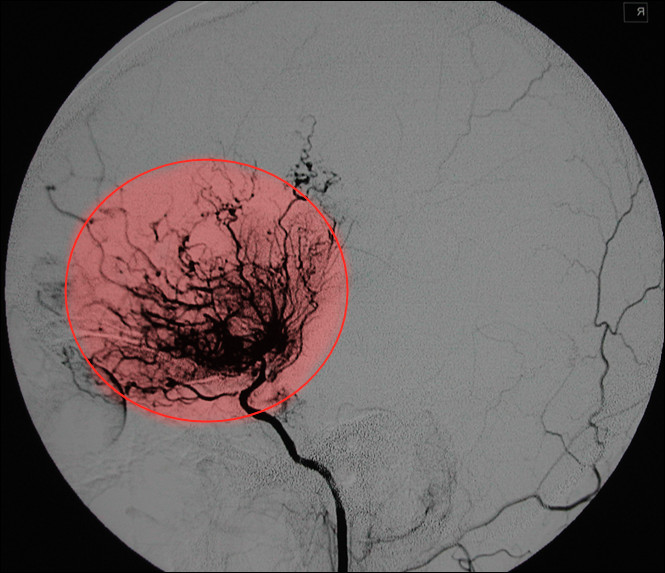

突然头晕头痛,肢体无力,说不出话,很有可能是烟雾病搞的鬼!烟雾病是一种病因不明、慢性进行性的脑血管闭塞性疾病,主要表现为单侧或双侧颈内动脉远端大脑中动脉和大脑前动脉近端狭窄或闭塞伴脑底部和软脑膜烟雾状、细小血管形成。最早的时候是由日本人发现,因脑血管造影显示的异常细小血管形似烟雾,所以以形命名,称之为烟雾病,与吸烟无关。(如下图)虽然烟雾病发现于日本,但是在中国、韩国更为常见,大概为10万/3,有家族史的发病率更高,是正常人的42倍。